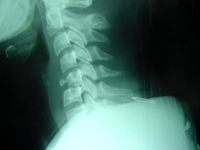

Las lesiones de la columna vertebral pueden clasificarse en tres tipos:

- El tipo de lesión más frecuente y menos grave es la fractura-acuñamiento. Se caracteriza porque el cuerpo vertebral, habitualmente cuadrado, adquiere la forma de una cuña en su región anterior. Muy raramente se asocia a una lesión neurológica.